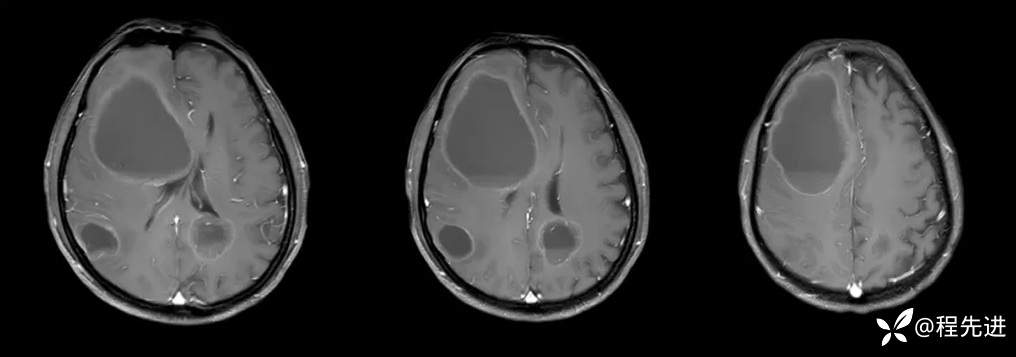

T1增强: